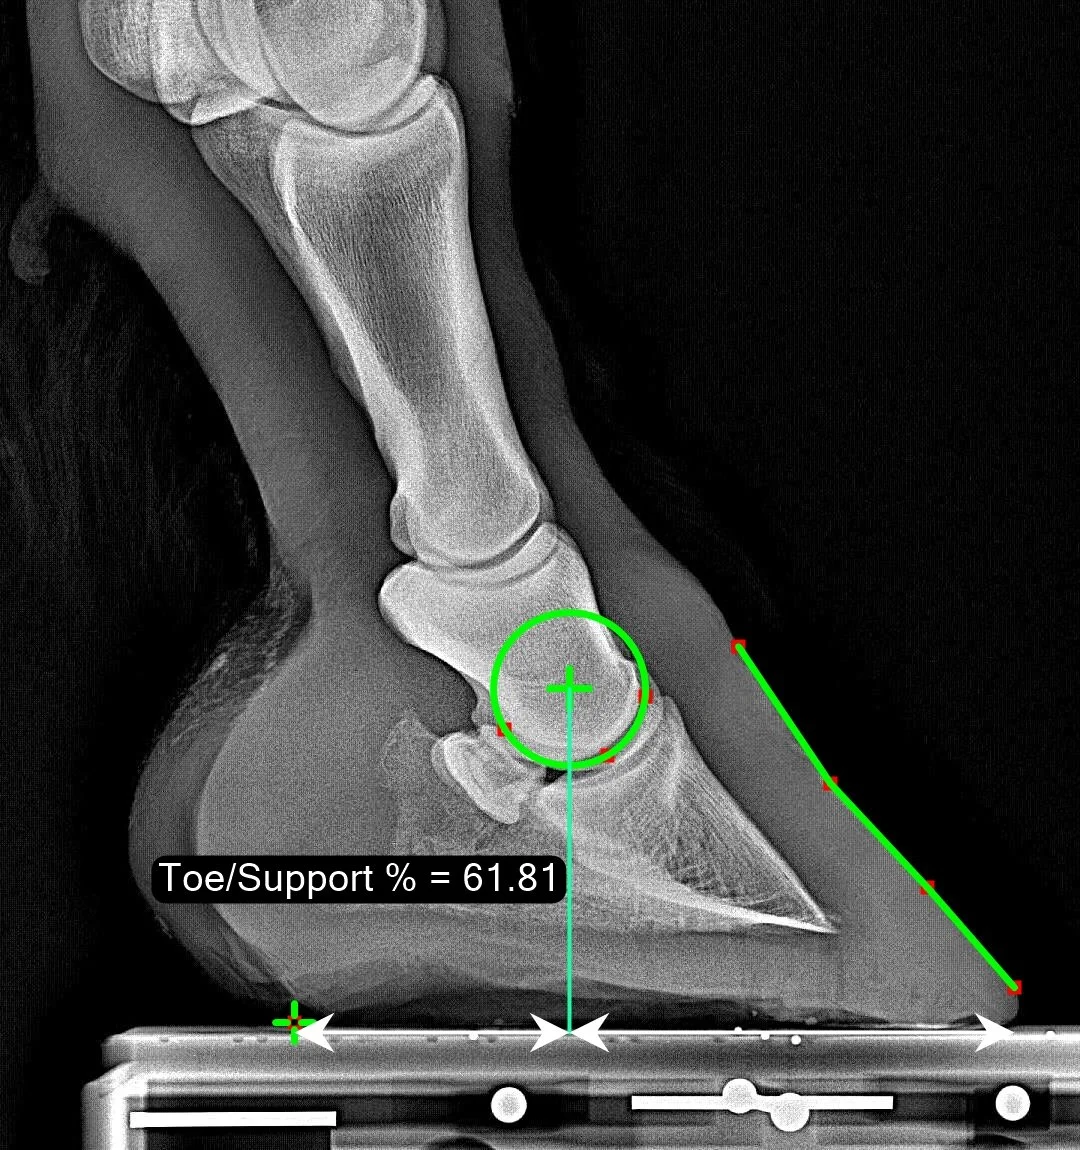

Toe/Support Percentage

The Toe/Support Percentage is measured as follows: a vertical line is dropped down from the center of articulation of the coffin joint. Then we measure the percentage of the ‘support length’ of the foot which lies ahead (cranial) to this line. The ‘support length’ extends from the most caudal point where the hard heel meets the ground, up to the most cranial part of the hoof. In the case of a ‘toe bevel’ this might be defined differently but note that we extend it past where the bevel begins and go all the way to the most cranial tip of the hoof. This measure can be thought of as a biomechanically-inspired measure of toe length. A larger value means a longer toe, and a bigger lever arm during breakover.

Normal Range

The normal range we observe is from 60.3% up to 69.8% with a median of 64.9%.